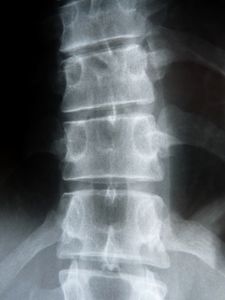

Sie sind hier: Startseite Nachrichten Gesundheit Jeder zwölfte Fehltag aufgrund von Rückenschmerzen Rückenschmerzen: Paracetamol hilft nicht. Bild: pixelio.de, Dieter Schütz

Rückenschmerzen: Paracetamol hilft nicht. Bild: pixelio.de, Dieter Schütz